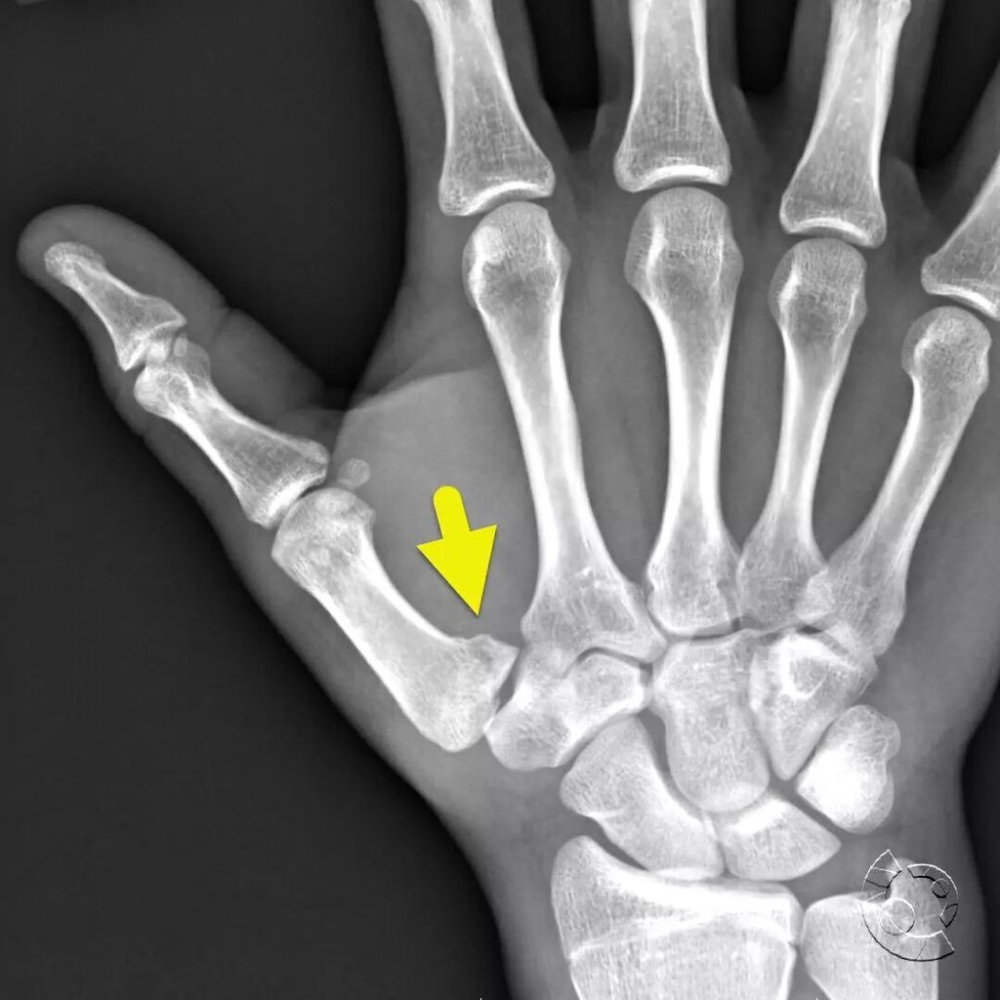

A fractured thumb can significantly affect a player's ability to perform, especially in a sport like cricket where grip and hand dexterity are crucial. The injury can occur in various ways, from falling on the thumb to excessive twisting or overstretching. A break in the thumb typically involves one or both of the thumb’s two bones: the distal phalange (tip of the thumb) and the proximal phalange (closer to the hand). As per Dr Seema Yadav, MD Physician, Care Institute of Life Sciences, Lucknow, thumb fractures may result in several noticeable symptoms, including:

The treatment for a thumb fracture can vary significantly. For minor fractures, a doctor might opt for a splint or cast to hold the thumb in place while it heals. In more severe cases, surgery may be required to realign the bones and stabilise the joint using pins, plates, or screws.

The recovery period for a broken thumb typically ranges from 4 to 6 weeks, during which time the patient may need to wear a cast or brace. Following the removal of the cast, physical therapy is often recommended to restore strength and mobility in the thumb. This process can take several months, as full function is often not regained until about three months after the injury. It’s important to follow the doctor’s instructions carefully to ensure proper healing. Failure to properly treat a thumb fracture could result in long-term complications, including arthritis, chronic pain, and limited movement in the thumb.